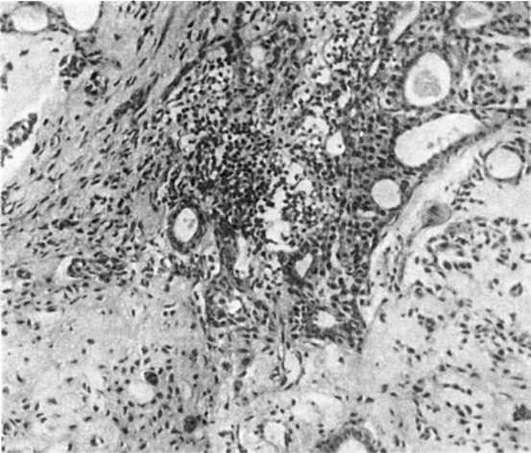

Плеоморфная аденома - самая частая эпителиальная опухоль слюнных желез, составляющая более 50% опухолей этой локализации. Почти в 90% случаев она локализуется в околоушной железе. Опухоль встречается чаще у людей старше 40 лет, но может наблюдаться в любом возрасте. У женщин она бывает в 2 раза чаще, чем у мужчин. Растет опухоль медленно (10-15 лет). Опухоль представляет собой узел округлой или овальной формы, иногда бугристой, плотноватой или эластической консистенции, размером до 5-6 см. Опухоль окружена тонкой капсулой. На разрезе ткань опухоли белесоватая, часто ослизненная, с мелкими кистами.Гистологически опухоль чрезвычайно разнообразна, за что и получила название плеоморфной аденомы. Эпителиальные образования имеют структуру протоков, солидных полей, отдельных гнезд, анастомо-

зирующих между собой тяжей, построенных из клеток округлой, полигональной, кубической, иногда цилиндрической, формы. Часты скопления клеток миоэпителия вытянутой веретенообразной формы со светлой цитоплазмой. Кроме эпителиальных структур характерно наличие очагов и полей мукоидного, миксоидного и хондроидного вещества (рис. 362), которое является продуктом секреции миоэпителиальных клеток, подвергшихся опухолевой трансформации. В опухоли могут встречаться очаги гиалиноза стромы, в эпителиальных участках - ороговение.

Рис.

362. Плеоморфная аденома